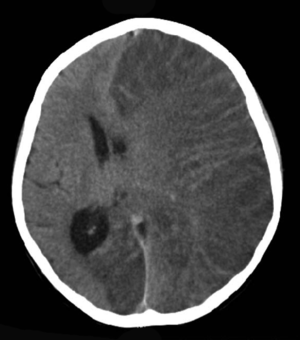

Brain CT scan of a girl with Rasmussen's encephalitis.

Rasmussen's encephalitis, also known as chronic focal encephalitis (CFE), is a rare inflammatory neurological disease, characterized by frequent and severe seizures, loss of motor skills and speech, hemiparesis (paralysis on one side of the body), encephalitis (inflammation of the brain), and dementia. The illness affects a single cerebral hemisphere and generally occurs in children under the age of 15.